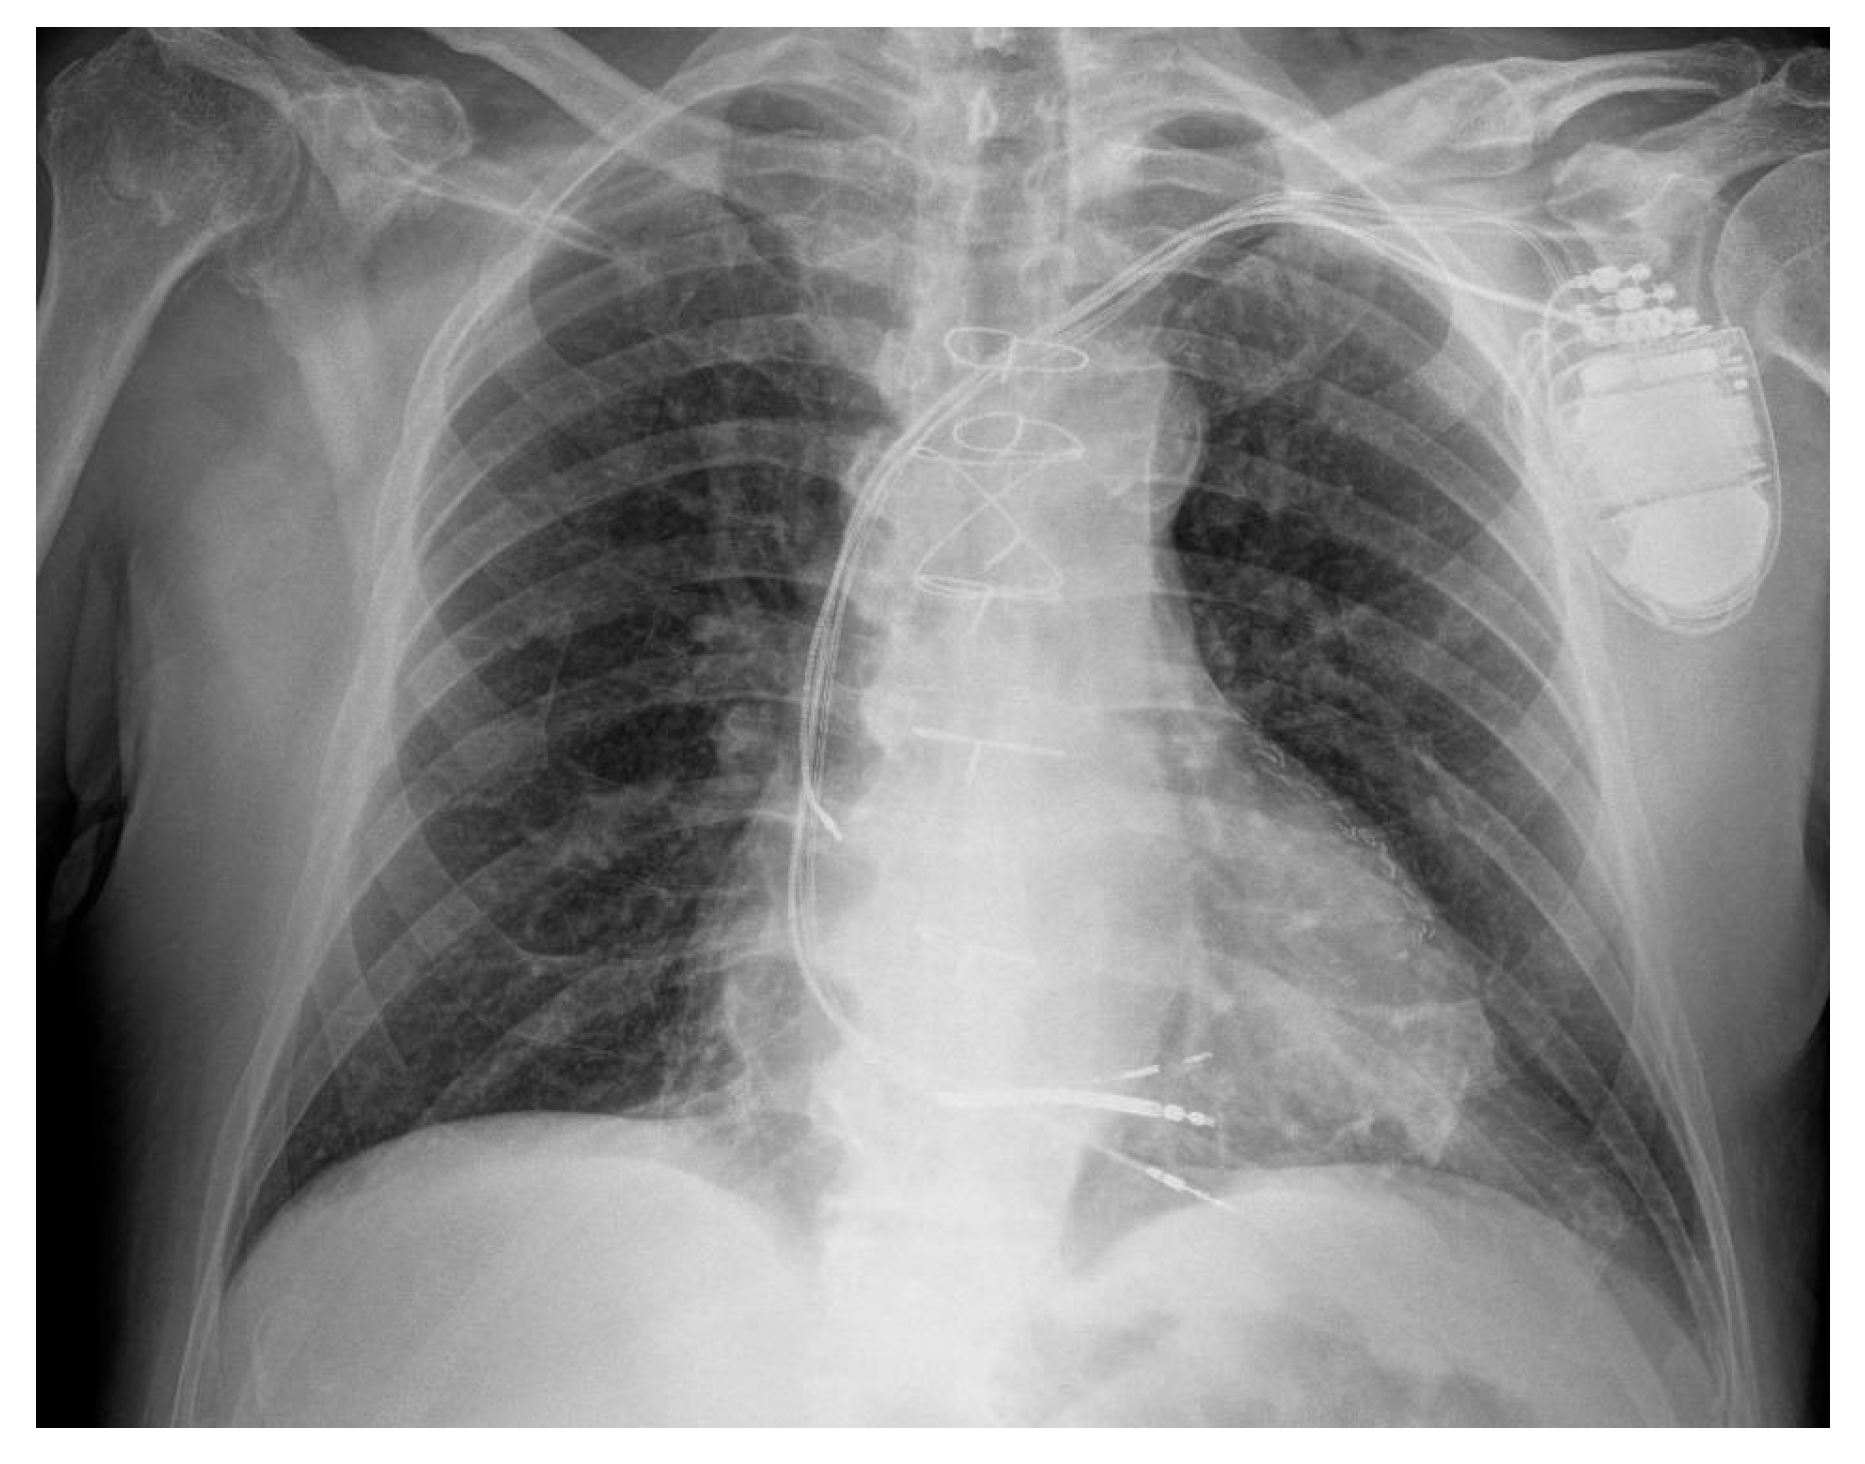

2. Case Presentation